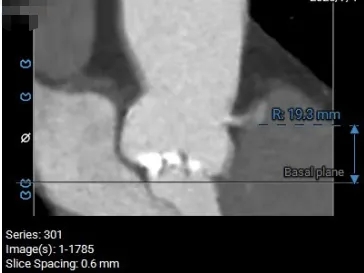

术前CT分析

主动脉根部测量

Annulus 20.7mm

LVOT 21.3mm

钙化积分 612

SOV

27.9*26.8*27.1mm

STJ 22.6mm

AAO 28.8mm

瓣上结构测量

瓣上2mm

20.5mm

瓣上4mm

19.9mm

瓣上6mm

20.7mm

瓣上8mm

20.2mm

瓣上10mm

20.8mm

瓣上12mm

21.9mm